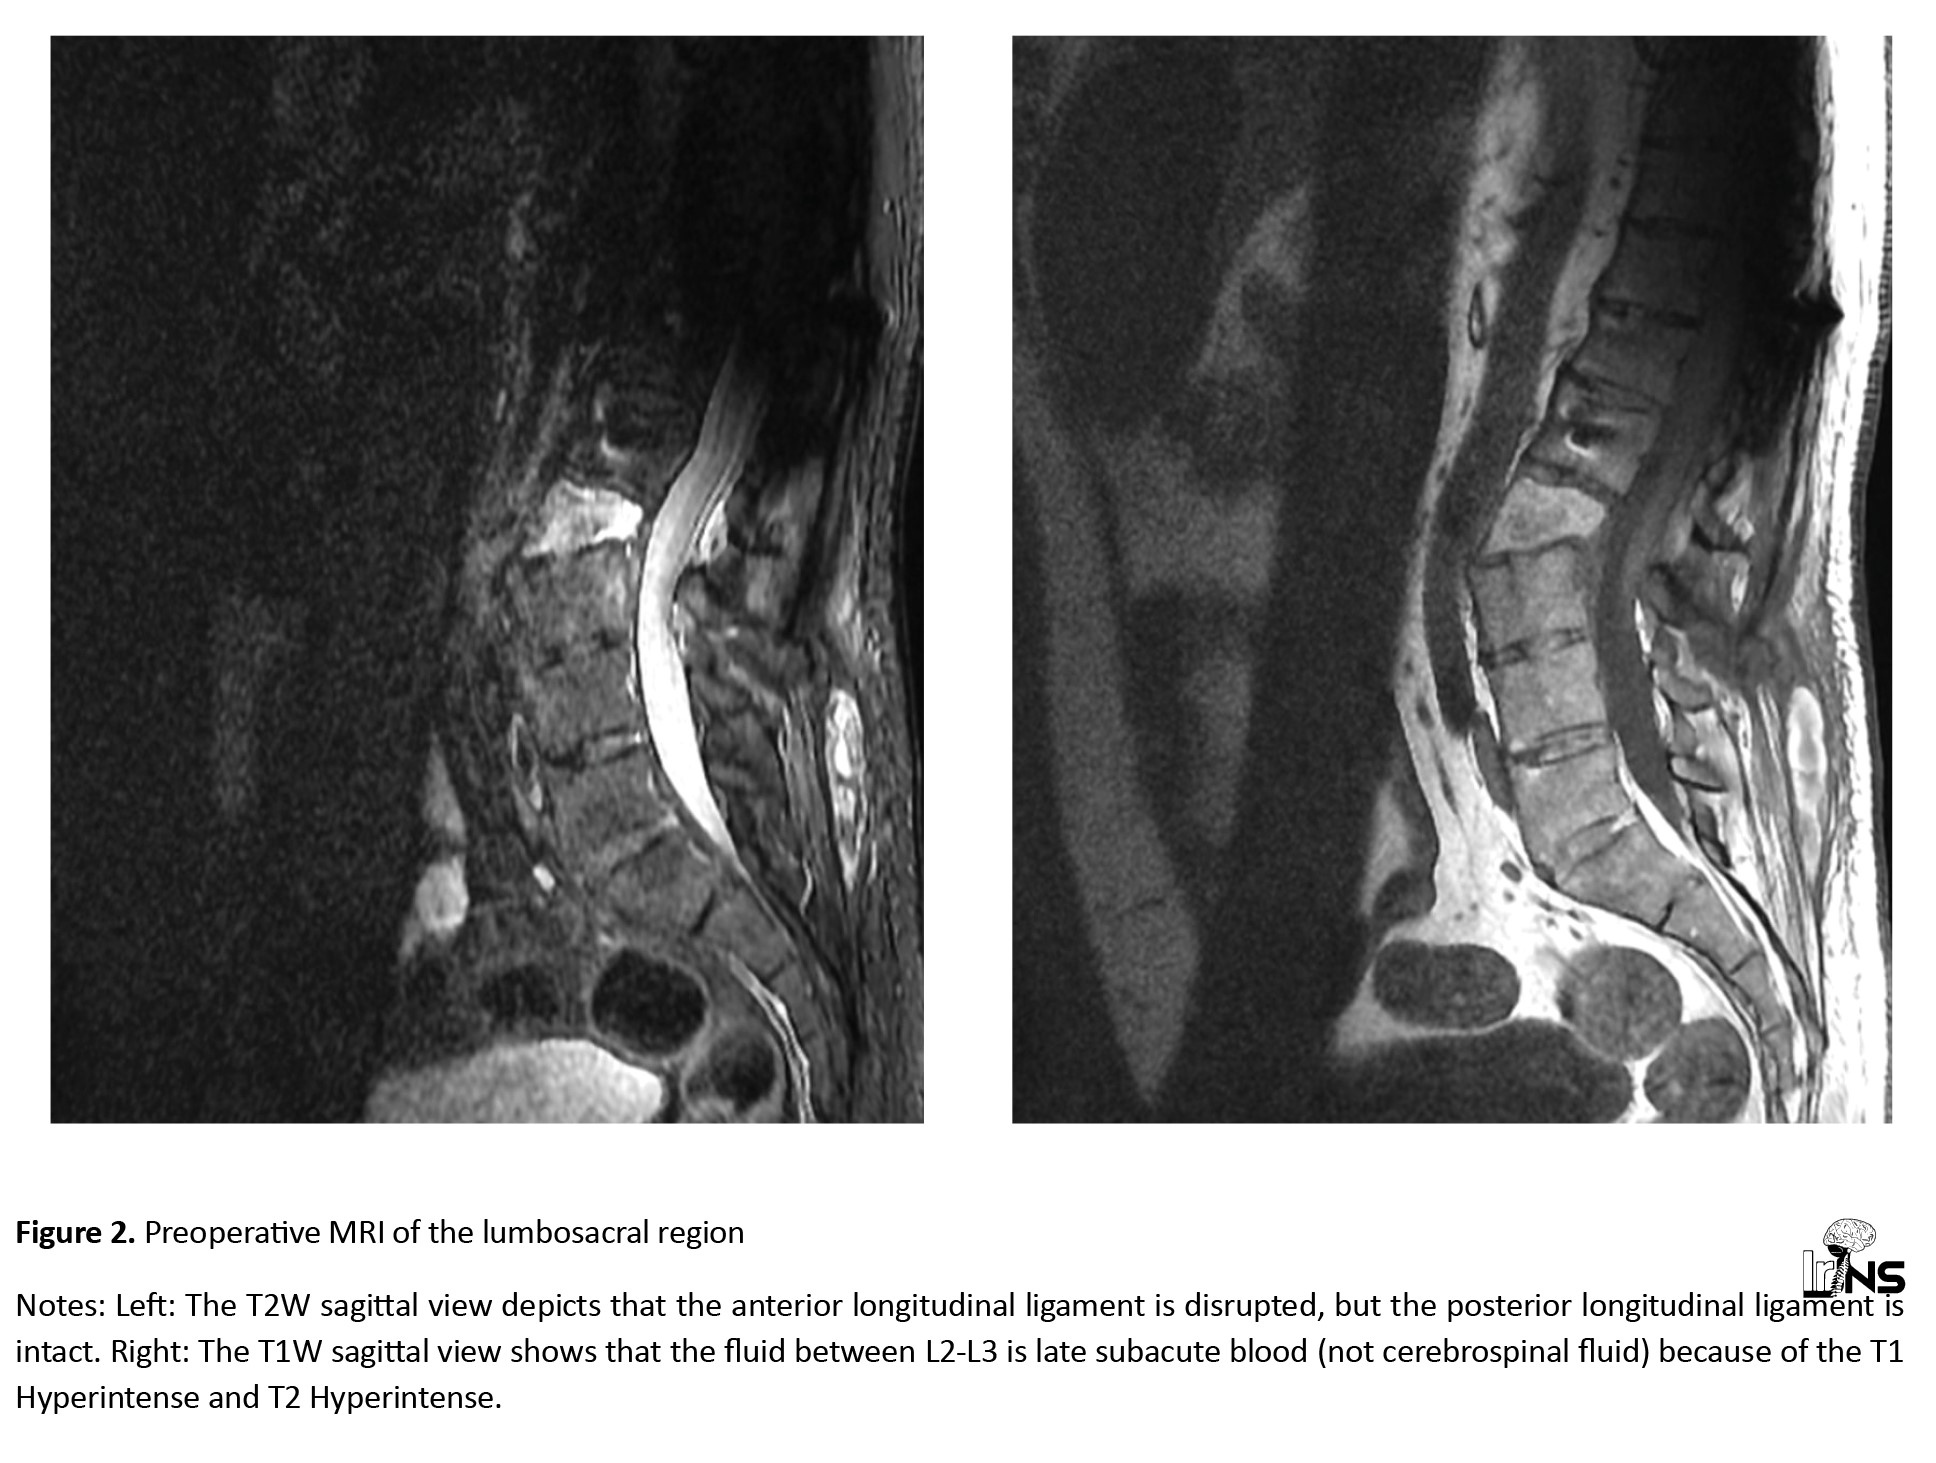

A computed tomography (CT) scan revealed a fracture translation in the L2-L3 intervertebral disc level. The translation was more significant in the sagittal plane than in the coronal plane. According to the Arbeitsgemeinschaft für Osteosynthesefragen (AO) classification, this was a type C fracture-dislocation. A whole-spine CT had no other significant findings (Figure 1).